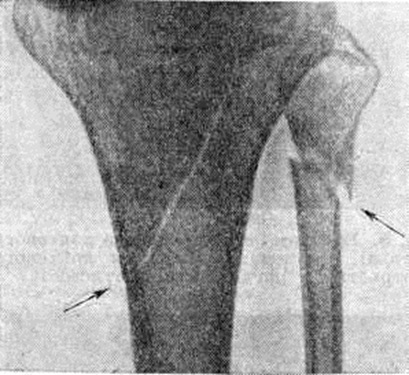

Основной рентгенологическое признак нарушения целости кости — линия Переломы Большое диагностическое значение имеет смещение отломков, наличие которого настолько бесспорно доказывает нарушение целости кости, что надобность в дифференциальной диагностике отпадает. Как бы подробно ни была описана рентгенологическое картина Переломы, наиболее полное и правильное представление о степени и характере смещения отломков врач может составить лишь при непосредственном просмотре снимков. Захождение отломков одного за другим при продольном смещении на рентгенограмме в одной проекции может сопровождаться наслоением теней концов отломков — так называемый суперпозицией теней. В этом случае точное определение смещения отломка возможно на основании данных снимков во второй проекции. При Переломы плоских костей (лопатка, ребра, таз и другие), при которых по техническим причинам производство снимка во второй проекции затруднено, суперпозиция отломков часто является единственным достоверным признаком Переломы Распознавание продольных смещений с расхождением отломков обычно не представляет каких либо затруднений. Подобного рода смещения наблюдаются при Переломы надколенника с разрывом связочного аппарата, локтевого отростка, вертелов бедра, отрывах костных выступов, к которым прикрепляются мышцы, сокращающиеся при повреждениях и приводящие к расхождению. Интерпозиция мягких тканей между отломками костей при рентгенологическое исследовании не распознается. Различные виды Переломы в наиболее информативных проекциях представлены на рисунок 4—11.